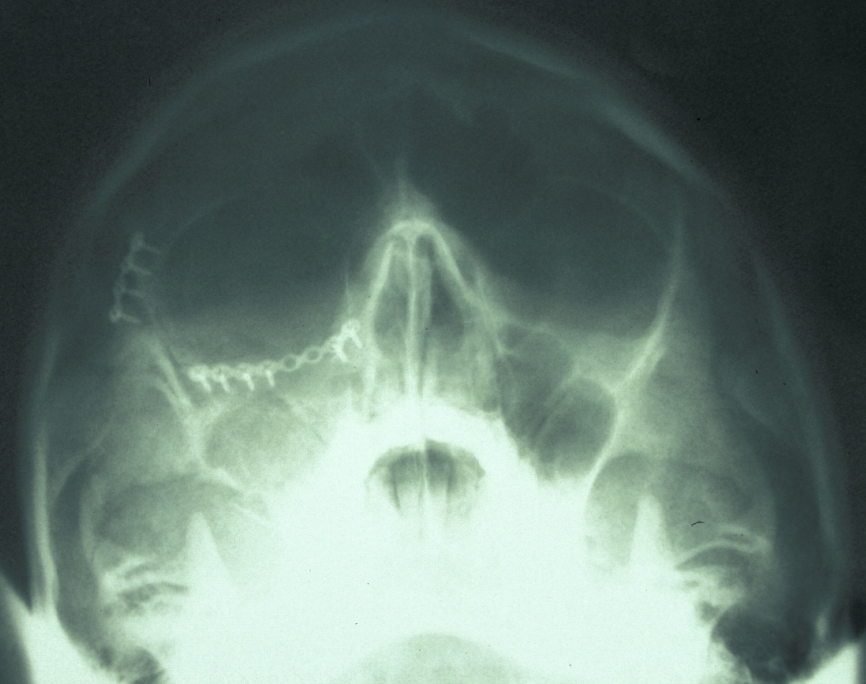

Definitive surgery usually involves open reduction and internal fixation (ORIF) under general anaesthesia, ideally using nasoendotracheal intubation. This allows the patient’s mouth to be closed and the teeth to be manipulated into their normal occlusion. This manipulation helps reduce the mandible into the prefracture bone position. Temporary intermaxillary fixation (IMF) is applied using a variety of techniques (trainee’s hand, eyelets, transalveolar screws (see Figure 1 and Figure 2), ‘rapid IMF’, arch bars). This helps to hold the fracture in its reduced position. Placing a bridle wire or tension band around the teeth can help reduce and temporarily fix the fracture.

Under direct vision via buccal sulcus incisions (incision in the depression between cheek and arch of jaw) the mandibular fracture is exposed and reduction confirmed (see Figure 3).